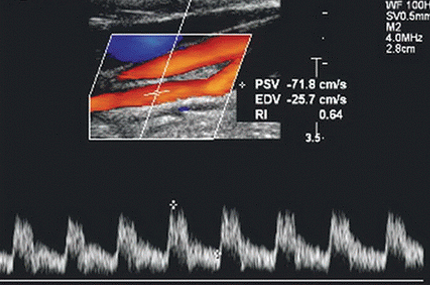

What pathology is being shown in this image?

Stenosis

What Doppler feature is demonstrated in the spectral waveform?

Spectral broadening indicating disturbed/turbulent flow

Based on the Doppler image, which finding best characterizes the hemodynamics at the sampled site?

Focal flow acceleration with spectral broadening consistent with a stenotic jet

Elevated velocities associated with this finding may be detected:

Within the stenosis and extending into adjacent proximal and distal segments

Which combination of Doppler findings most strongly supports hemodynamically significant stenosis in this image?

Elevated peak velocities with spectral broadening and evidence of flow disturbance

The Doppler sample volume in this image is most likely located:

Distal to a stenosis

Identify TWO abnormal Doppler findings present in this image.

Spectral broadening + turbulent/chaotic flow with eddy currents